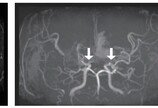

“피 검사로 확진”…소아 모야모야병 조기진단 길 열렸다간단한 혈액 검사만으로도 소아 모야모야병을 조기 진단할 수 있는 길이 열렸다.서울대병원은 김승기 소아신경외과 교수 연구팀이 소아 모야모야병(MMD)을 혈액 검사만으로 조기에 진단하고 치료 반응을 예측할 수 있는 새로운 바이오마커 ‘miR-512-3p’를 발견했다고 31일 밝혔다. 연구…2025-07-31 08:44:29